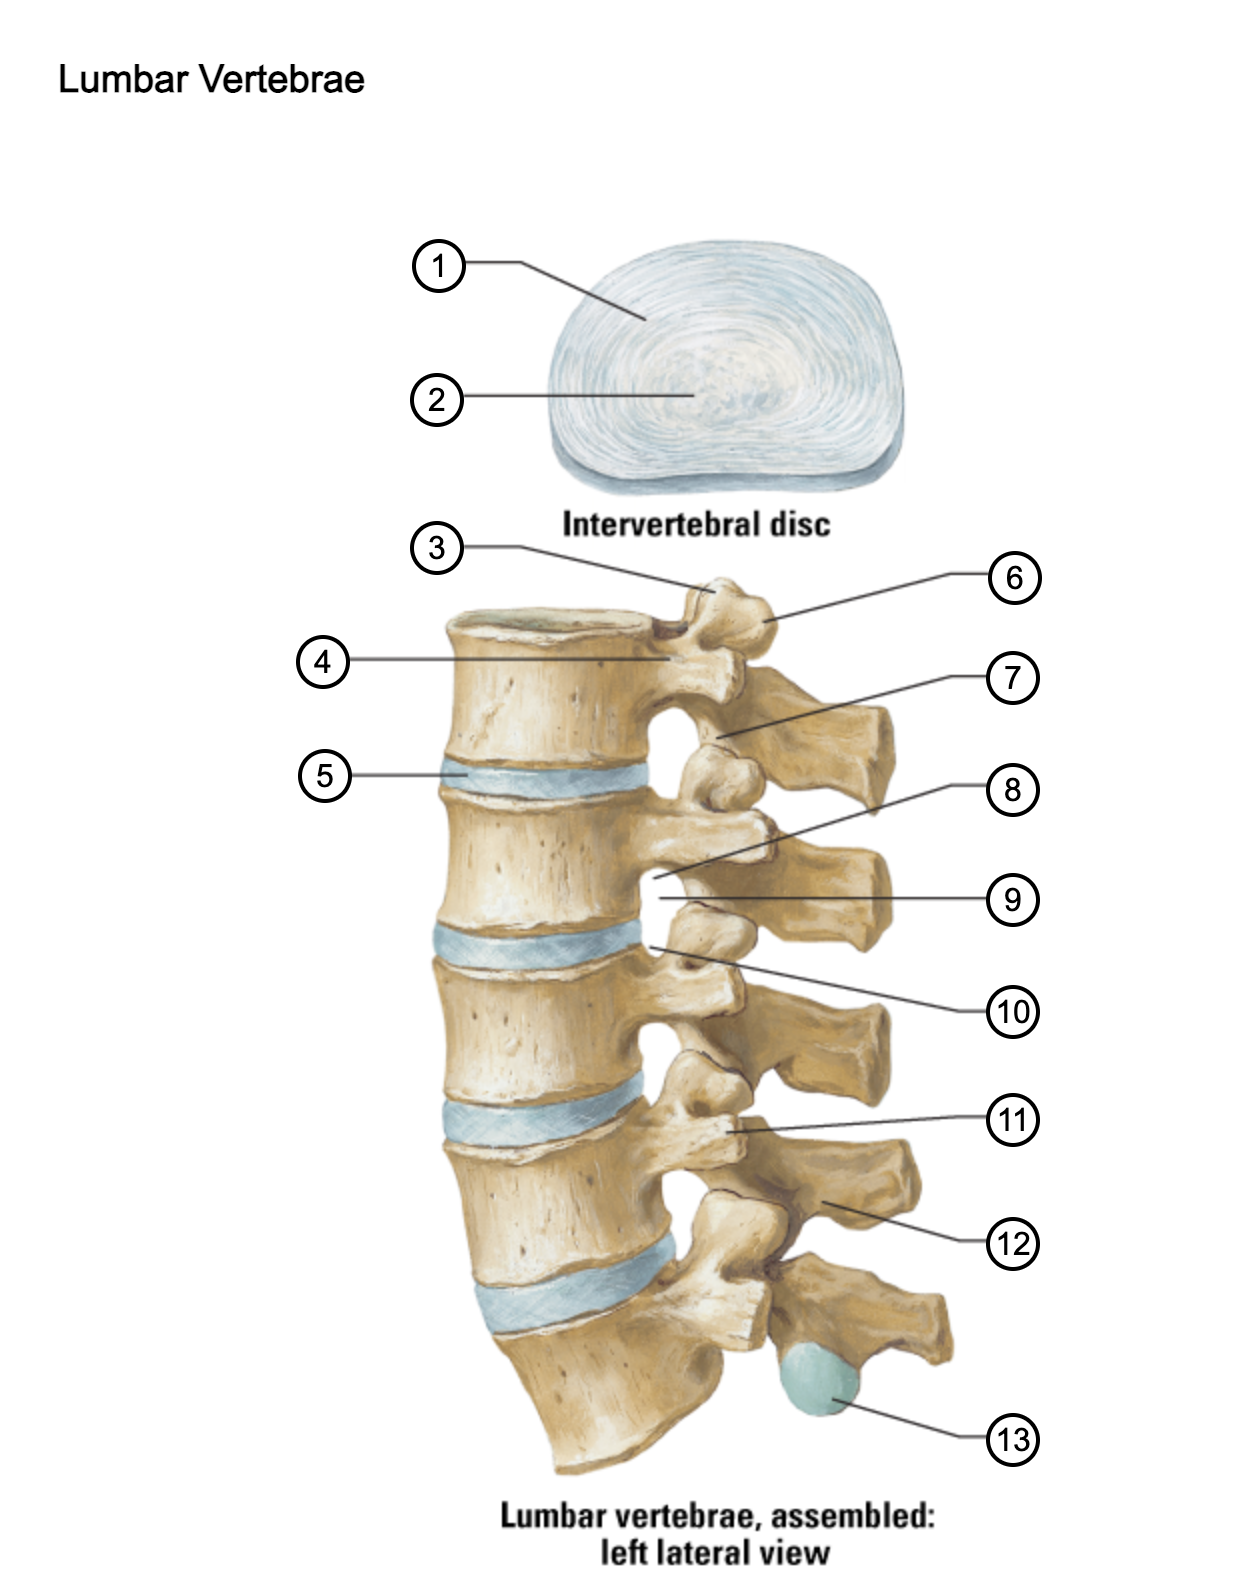

1

anulus fibrosus

2

nucleus pulposus

3

superior articular process

4

pedicle

5

intervertebral disc

6

mammillary process

7

inferior articular process

8

inferior vertebral notch

9

intervertebral notch

10

superior vertebral notch

11

transverse process

12

lamina

13

inferior articular facet